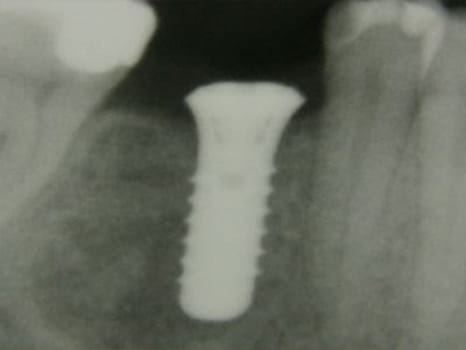

Zahnimplantate bestehen in der Regel aus Titan und werden sorgfältig im Kieferknochen eingeschraubt. Nach drei Monaten Einheilphase sind Implantate fest im Knochen verankert und können belastet werden. (vgl. Abbildung). Die künstliche Zahnwurzel (Implantat) ermöglicht es, Kronen, Brücken oder Elemente zur Verankerung von Prothesen und Epithesen langfristig zu befestigen.

Implantat-roentgen

Implantat nach 3-monatiger Einheilphase